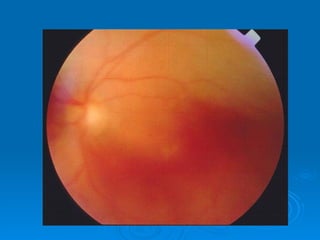

CRVO

 thrombosis of the central retinal vein

 sudden loss of vision in affected eye

 severity of symptoms varies…

   non-ischemic: 75%

   Ischemic

 most characteristic finding:   retinal

hemorrhages

 underlying associations

   advancing age

   systemic conditions: HTN, DM, smoking,

obesity, hyperlipidemia

   glaucoma

   inflammatory diseases: sarcoidosis, Behcet

disease

   thrombophilic disorders:

hyperhomocysteinaemia, antiphospholipid

antibody syndrome

 Treatment:

   treat associated medical conditions

   decrease IOP if elevated

   pan-retinal photocoagulation

(laser) if:

• neovascularization (iris, angle,

retina)

• …especially if ischemic CRVO